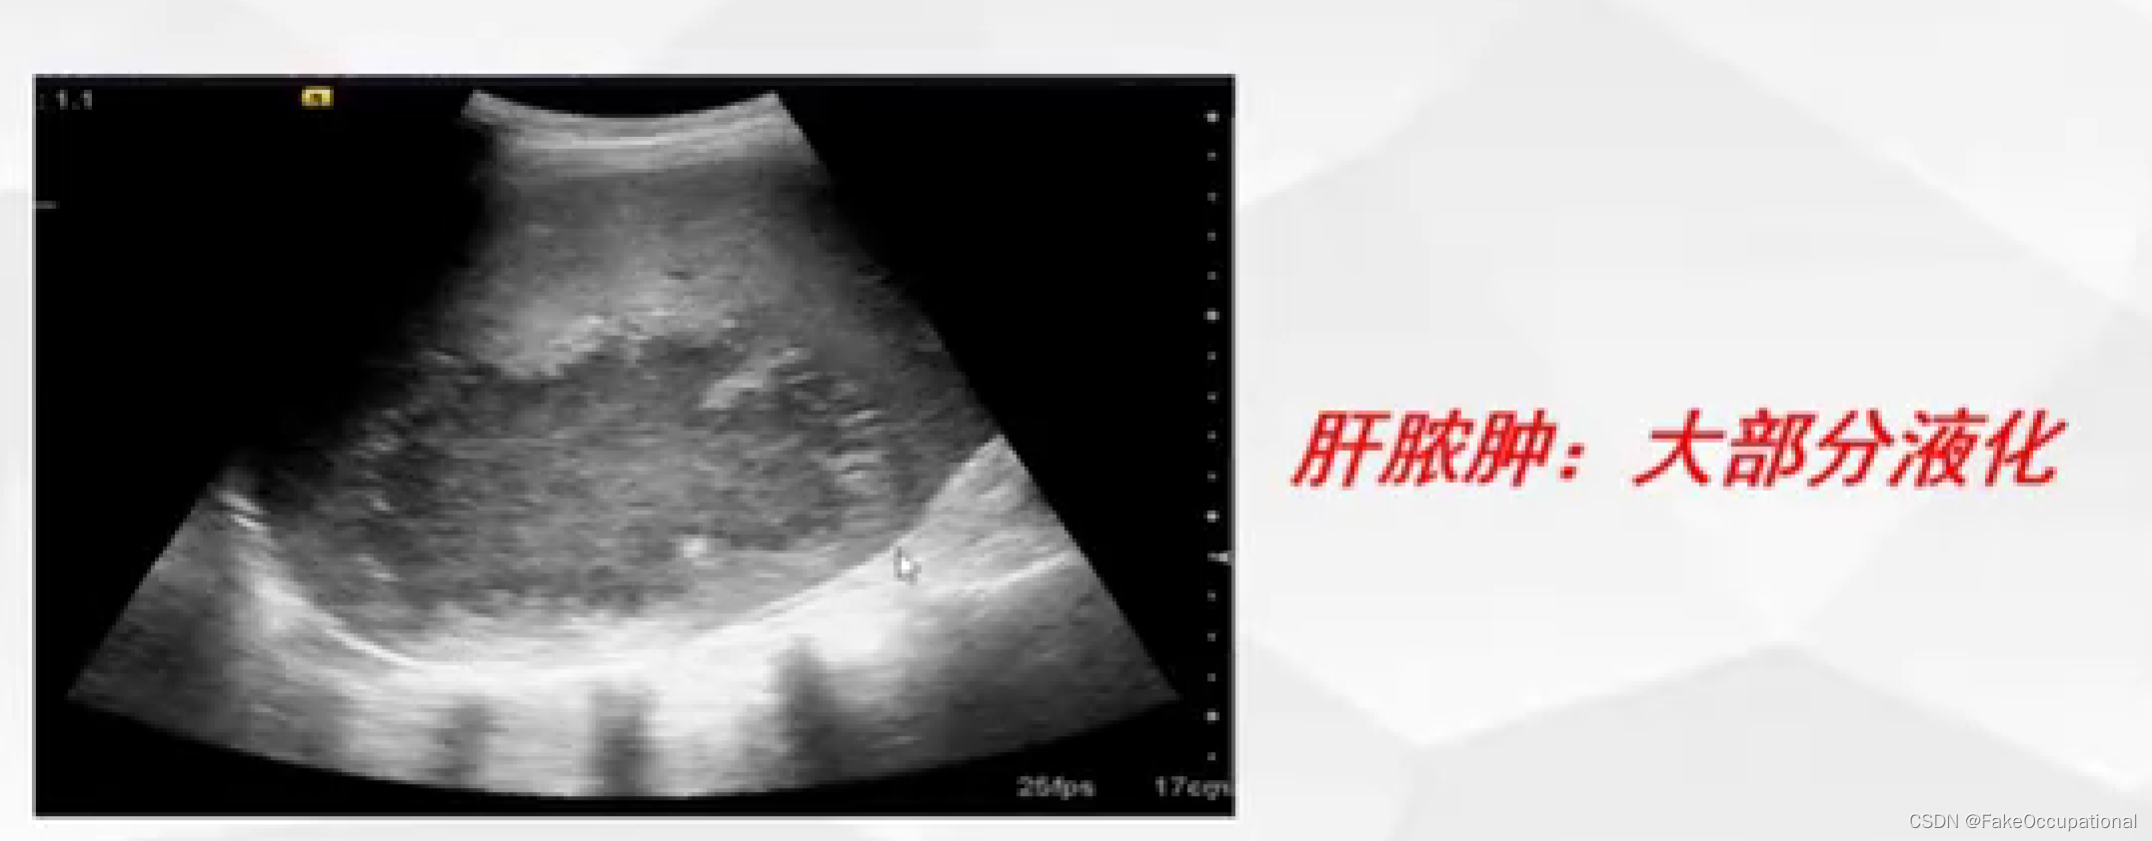

异常肝脏超声表现